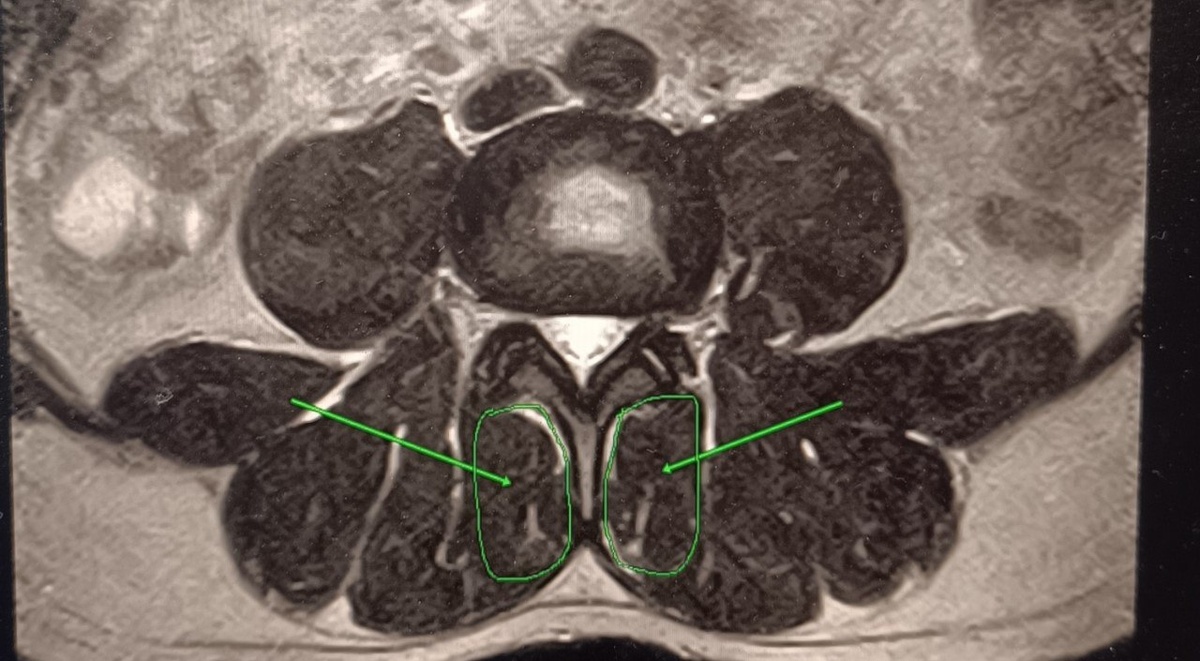

📸 На примере снимков:

— на первом фото — здоровые мышцы: плотные, эластичные, хорошо выраженные

— на втором фото — патологические изменения: мышцы частично замещены соединительной тканью ( обведены в малые кружочки)

Особое внимание — многораздельным мышцам

Именно они являются глубокими стабилизаторами позвоночника.

Это мышцы, которые держат сегменты позвоночника в правильном положении при движении, сидении, нагрузке.